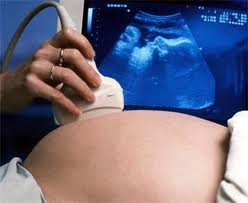

| Ảnh minh họa. |

Có nhiều loại dị tật bẩm sinh ở các cơ quan khác nhau. Các dị tật bẩm sinh thường là hậu quả tương tác của các yếu tố môi trường và gen. Dị tật bẩm sinh thường xảy ra sớm trước 18 tuần thai trong quá trình hình thành và biệt hóa về mặt hình thái và chức năng của các cơ quan.

Do chị không nêu rõ con đầu tiên bị dị tật bẩm sinh được chẩn đoán là loại gì, mức độ ra sao nên không thể trả lời cụ thể được. Khiếm khuyết ống thần kinh là loại thường gặp nhất và là loại có thể phòng ngừa rất hiệu quả bằng cách uống bổ sung viên axit folic trước và trong suốt thời gian mang thai. Chị có thể đến viện để được tư vấn tốt hơn.